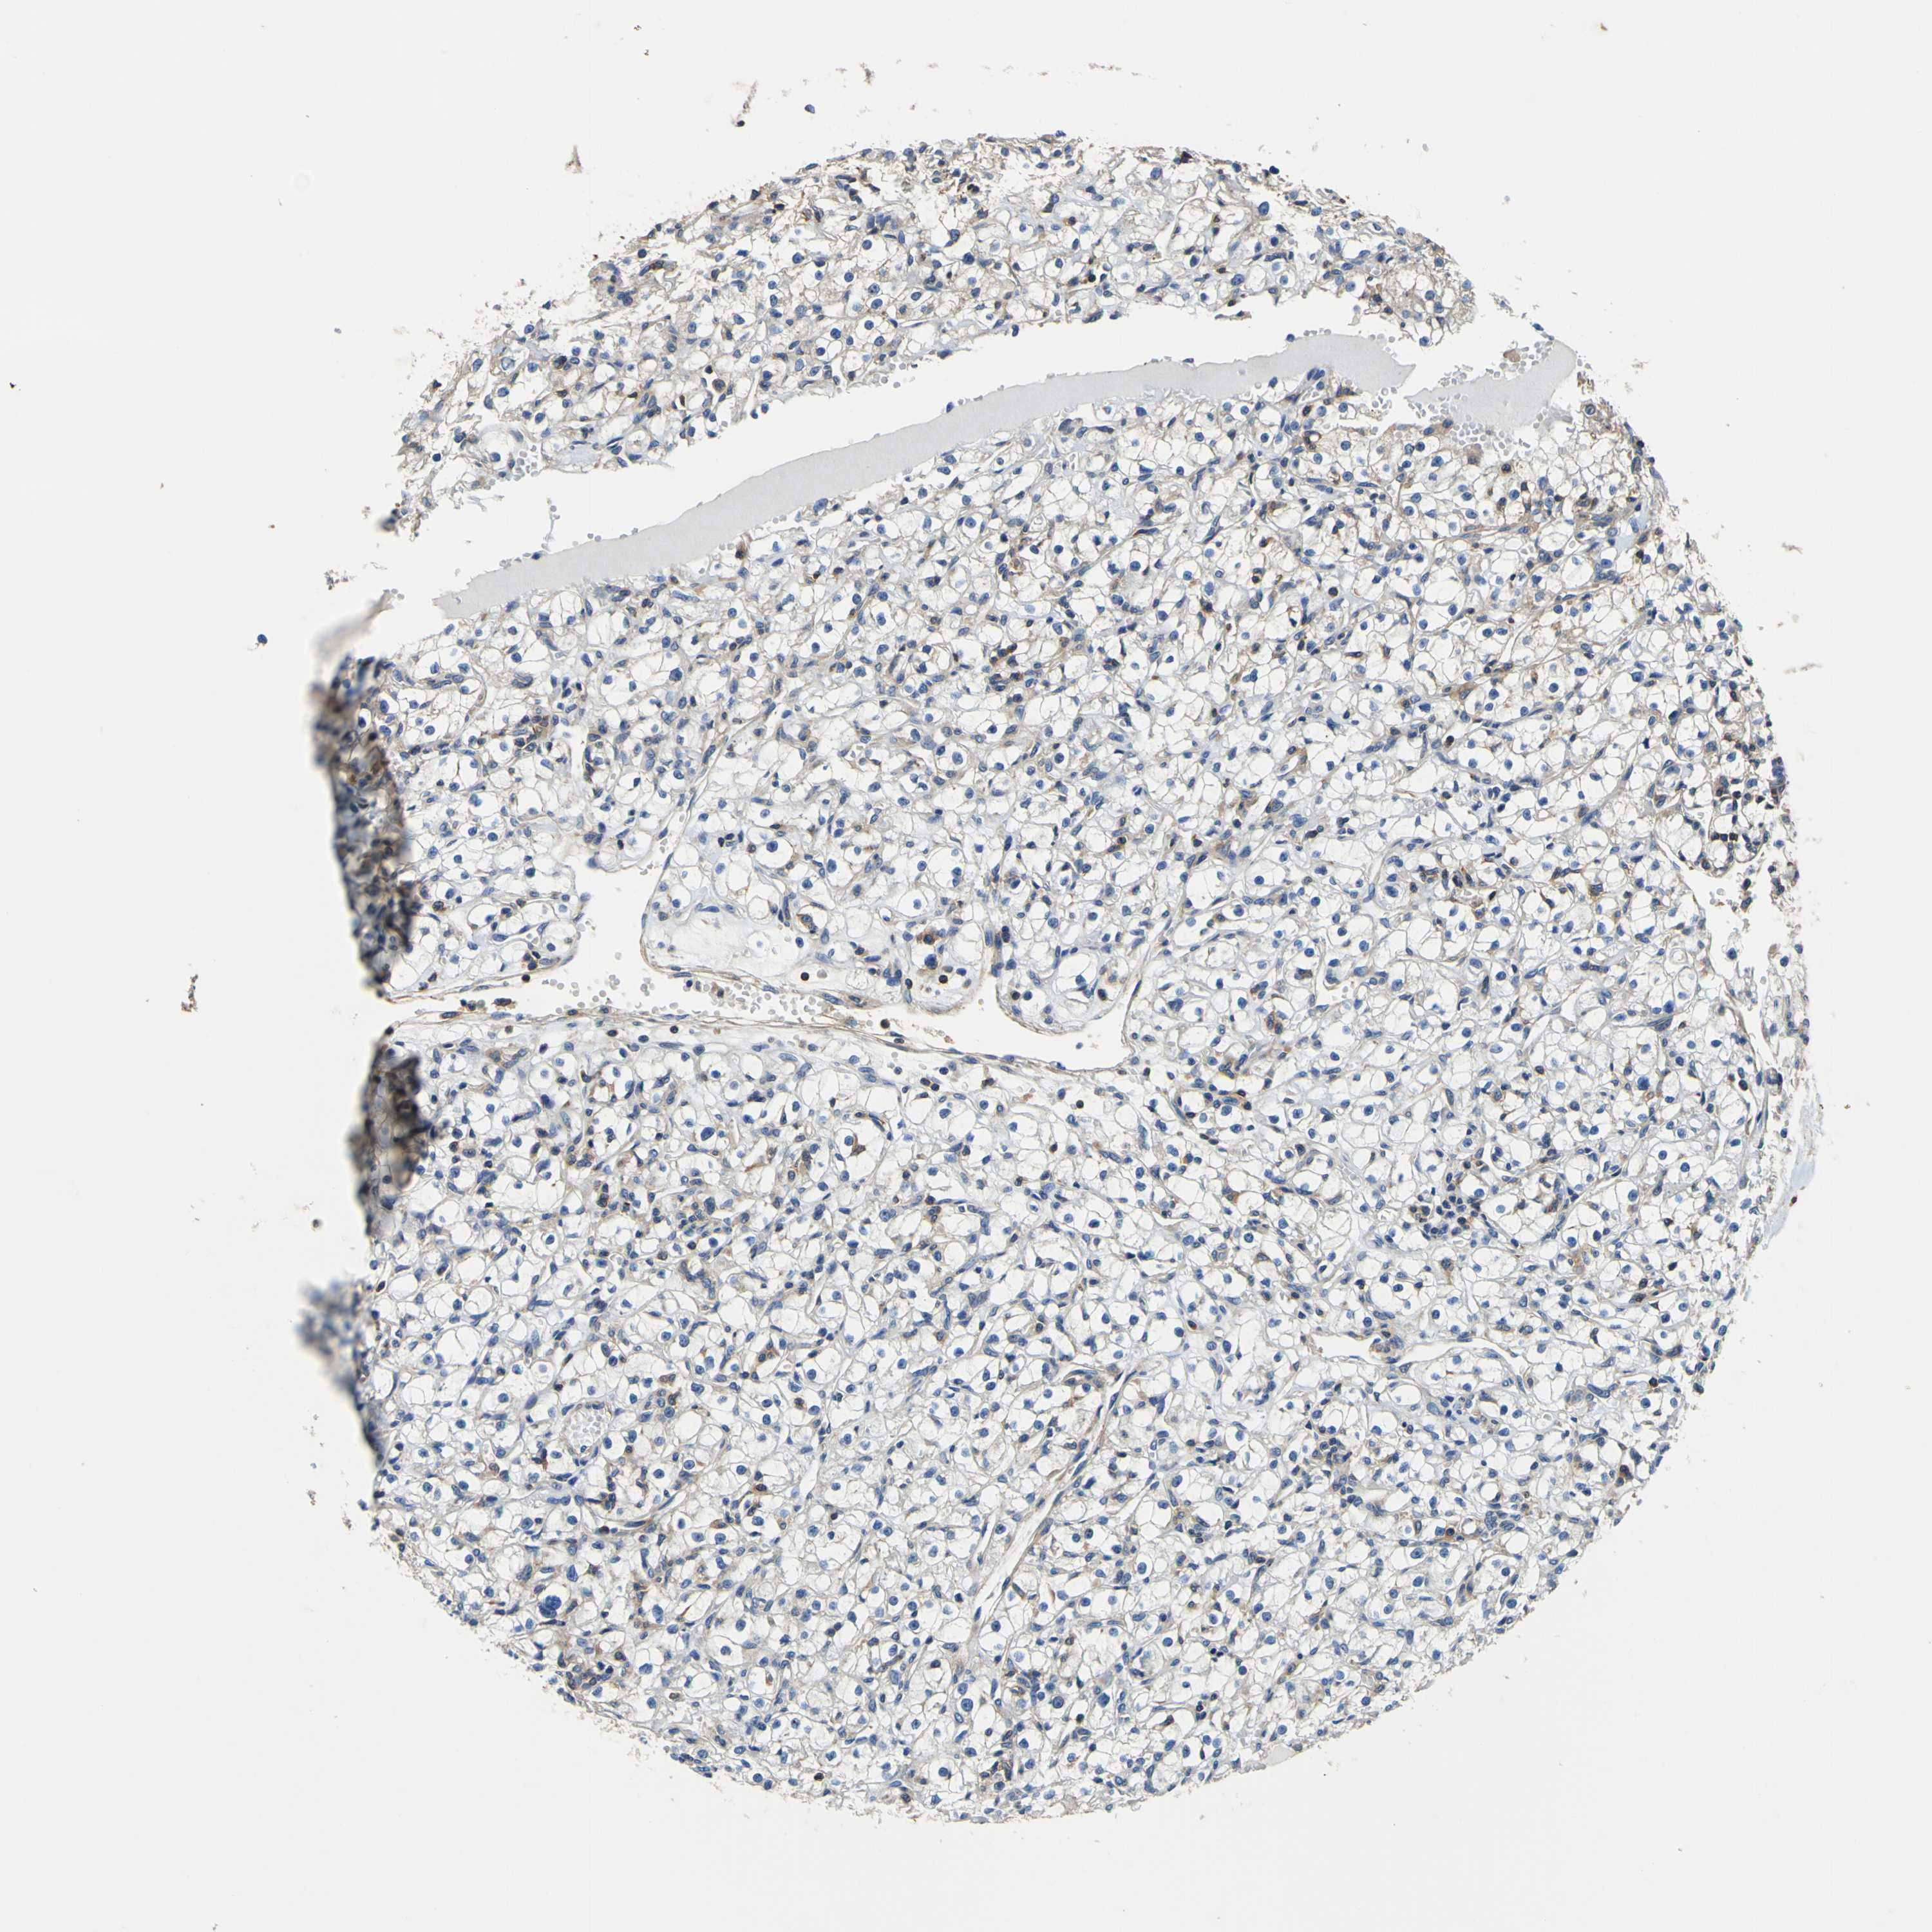

KIDNEY RENAL CLEAR CELL CARCINOMA (VALIDATION) - Interactive survival scatter ploti

The Survival Scatter plot shows the clinical status (i.e. dead or alive) for all individuals in the patient cohort, based on the same data that underlies the corresponding Kaplan-Meier plots. Patients that are alive at last time for follow-up are shown in blue and patients who have died during the study are shown in red.

The x-axis shows the expression levels (FPKM) of the investigated gene in the tumor tissue at the time of diagnosis. The y-axis shows the follow-up time after diagnosis (years). Both axes are complimented with kernel density curves demonstrating the data density over the axes. The top density plot shows the expression levels (FPKM) distribution among dead (red) and alive patients (blue). The right density plot shows the data density of the survived years of dead patients with high and low expression levels respectively, stratified using the cutoff indicated by the vertical dashed line through the Survival Scatter plot. This cutoff is automatically defined based on the FPKM cutoff that minimizes the p-score. The cutoff can be changed by dragging the vertical line or by entering a cutoff value in the square labeled "Current cut-off".

Under the Survival Scatter plot the p-score landscape (black curve; left axis) is shown together with dead median separation (red curve; right axis). Dead median separation is the difference in median mRNA expression between patients who have died with high and low expression, respectively. It is calculated as follows: median FPKM expression of dead patients with high expression - median FPKM expression of dead patients with low expression. This is intended to aid the user in visually exploring custom cutoffs and the associated p-scores and dead median separation.

Individual patient data is displayed and can be filtered by clicking on one or more of the category buttons on the top of the page. Categories describing expression level and patient information include: high, low, alive, dead, female, male and tumor stages. The scale of the x-axis can be toggled between linear and log-scale by clicking on the "x log" button. Mouse-over function shows TCGA ID, patient information and mRNA expression (FPKM) for each patient.

& Survival analysisi

Kaplan-Meier plots summarize results from analysis of correlation between mRNA expression level and patient survival. Patients were divided based on level of expression into one of the two groups "low" (under cut off) or "high" (over cut off). X-axis shows time for survival (years) and y-axis shows the probability of survival, where 1.0 corresponds to 100 percent.

CNR2 is not prognostic in Kidney Renal Clear Cell Carcinoma (validation)

TCGA RNA samplesi

RNA-seq data is reported as average FPKM (number Fragments Per Kilobase of exon per Million reads), generated by the The Cancer Genome Atlas (TCGA) .

Normal distribution across the dataset is visualized with box plots, shown as median and 25th and 75th percentiles. Points are displayed as outliers if they are above or below 1.5 times the interquartile range. FPKM values of the individual samples are presented next to the box plot.

Average pTPM 0.1

Number of samples 100